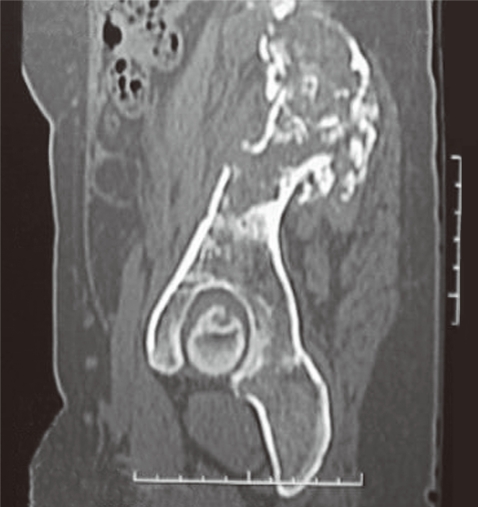

The patient continued with the pelvic pain although postoperative MRI showed reduction in size of the lesion along the right iliac bone and sacroiliac joint. No new lesion was, however, seen. The x-ray of the pelvis and hips revealed cortical irregularity with ill defined lytic defects and linear areas of patchy sclerosis along the right iliac blade (Fig. 1). She continued with pain and follow-up CT reviewed after 8 months revealed extension of the disease. The patient was then referred to our hospital. On physical examination, local tenderness was present on the back of the right limb and hip. The range of motion of the right hip was painful and restricted. No distal neurovascular deficits were present. Blood investigations were within normal range. Surgery was planned for removal of the residual disease. The preoperative MRI and CT showed progression of the disease. The CT showed a multiloculated cystic lesion (Fig. 2) involving the medullary cavity of the right iliac bone resulting in irregular lytic destruction and extending across the right sacroiliac joint into the right half of the sacrum, right sacral foramina, and adjacent soft tissues. Resection of the hydatid cyst of sacroiliac region with allograft and autograft (rib graft) with lumbosacroiliac fixation was done.